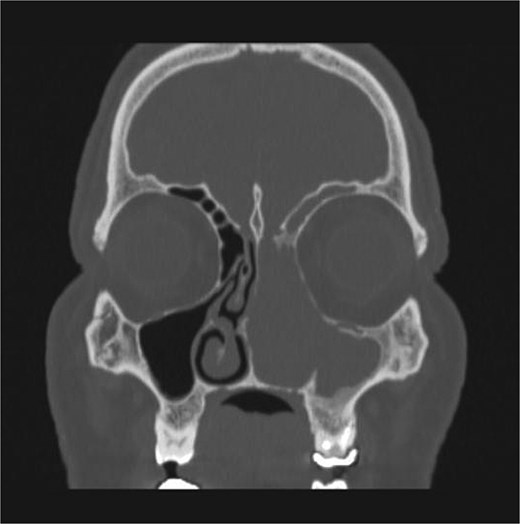

The patient underwent staging CT which was negative for distant metastasis. He then went underwent incomplete medial maxillectomy, ethmoidectomy, and sphenoidotomy followed by 10 sessions of immunotherapy abroad. He presented to our institution for follow up 6 months later with history of left nasal block and epistaxis. Nasal flexible scope showed a reddish nasal mass with greenish secretions (Fig. 3). Follow up CT revealed tumor recurrence (Figs 4 and 5). He was advised for multidisciplinary team evaluation to plan the treatment but he refused any intervention and lost follow up.

Coronal section of CT paranasal sinus soft tissue window showing the mass occupying the left nasal cavity and extending to maxillary and ethmoidal sinus, and reaching base of skull.